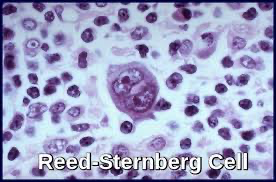

| Diagnostik: Lymphknotenbiopsie → Reed-Sternberg-Zellen | Diagnostik: Lymphknotenbiopsie → WHO-Klassifikation (B-/T-Zell; indolent vs. aggressiv) |